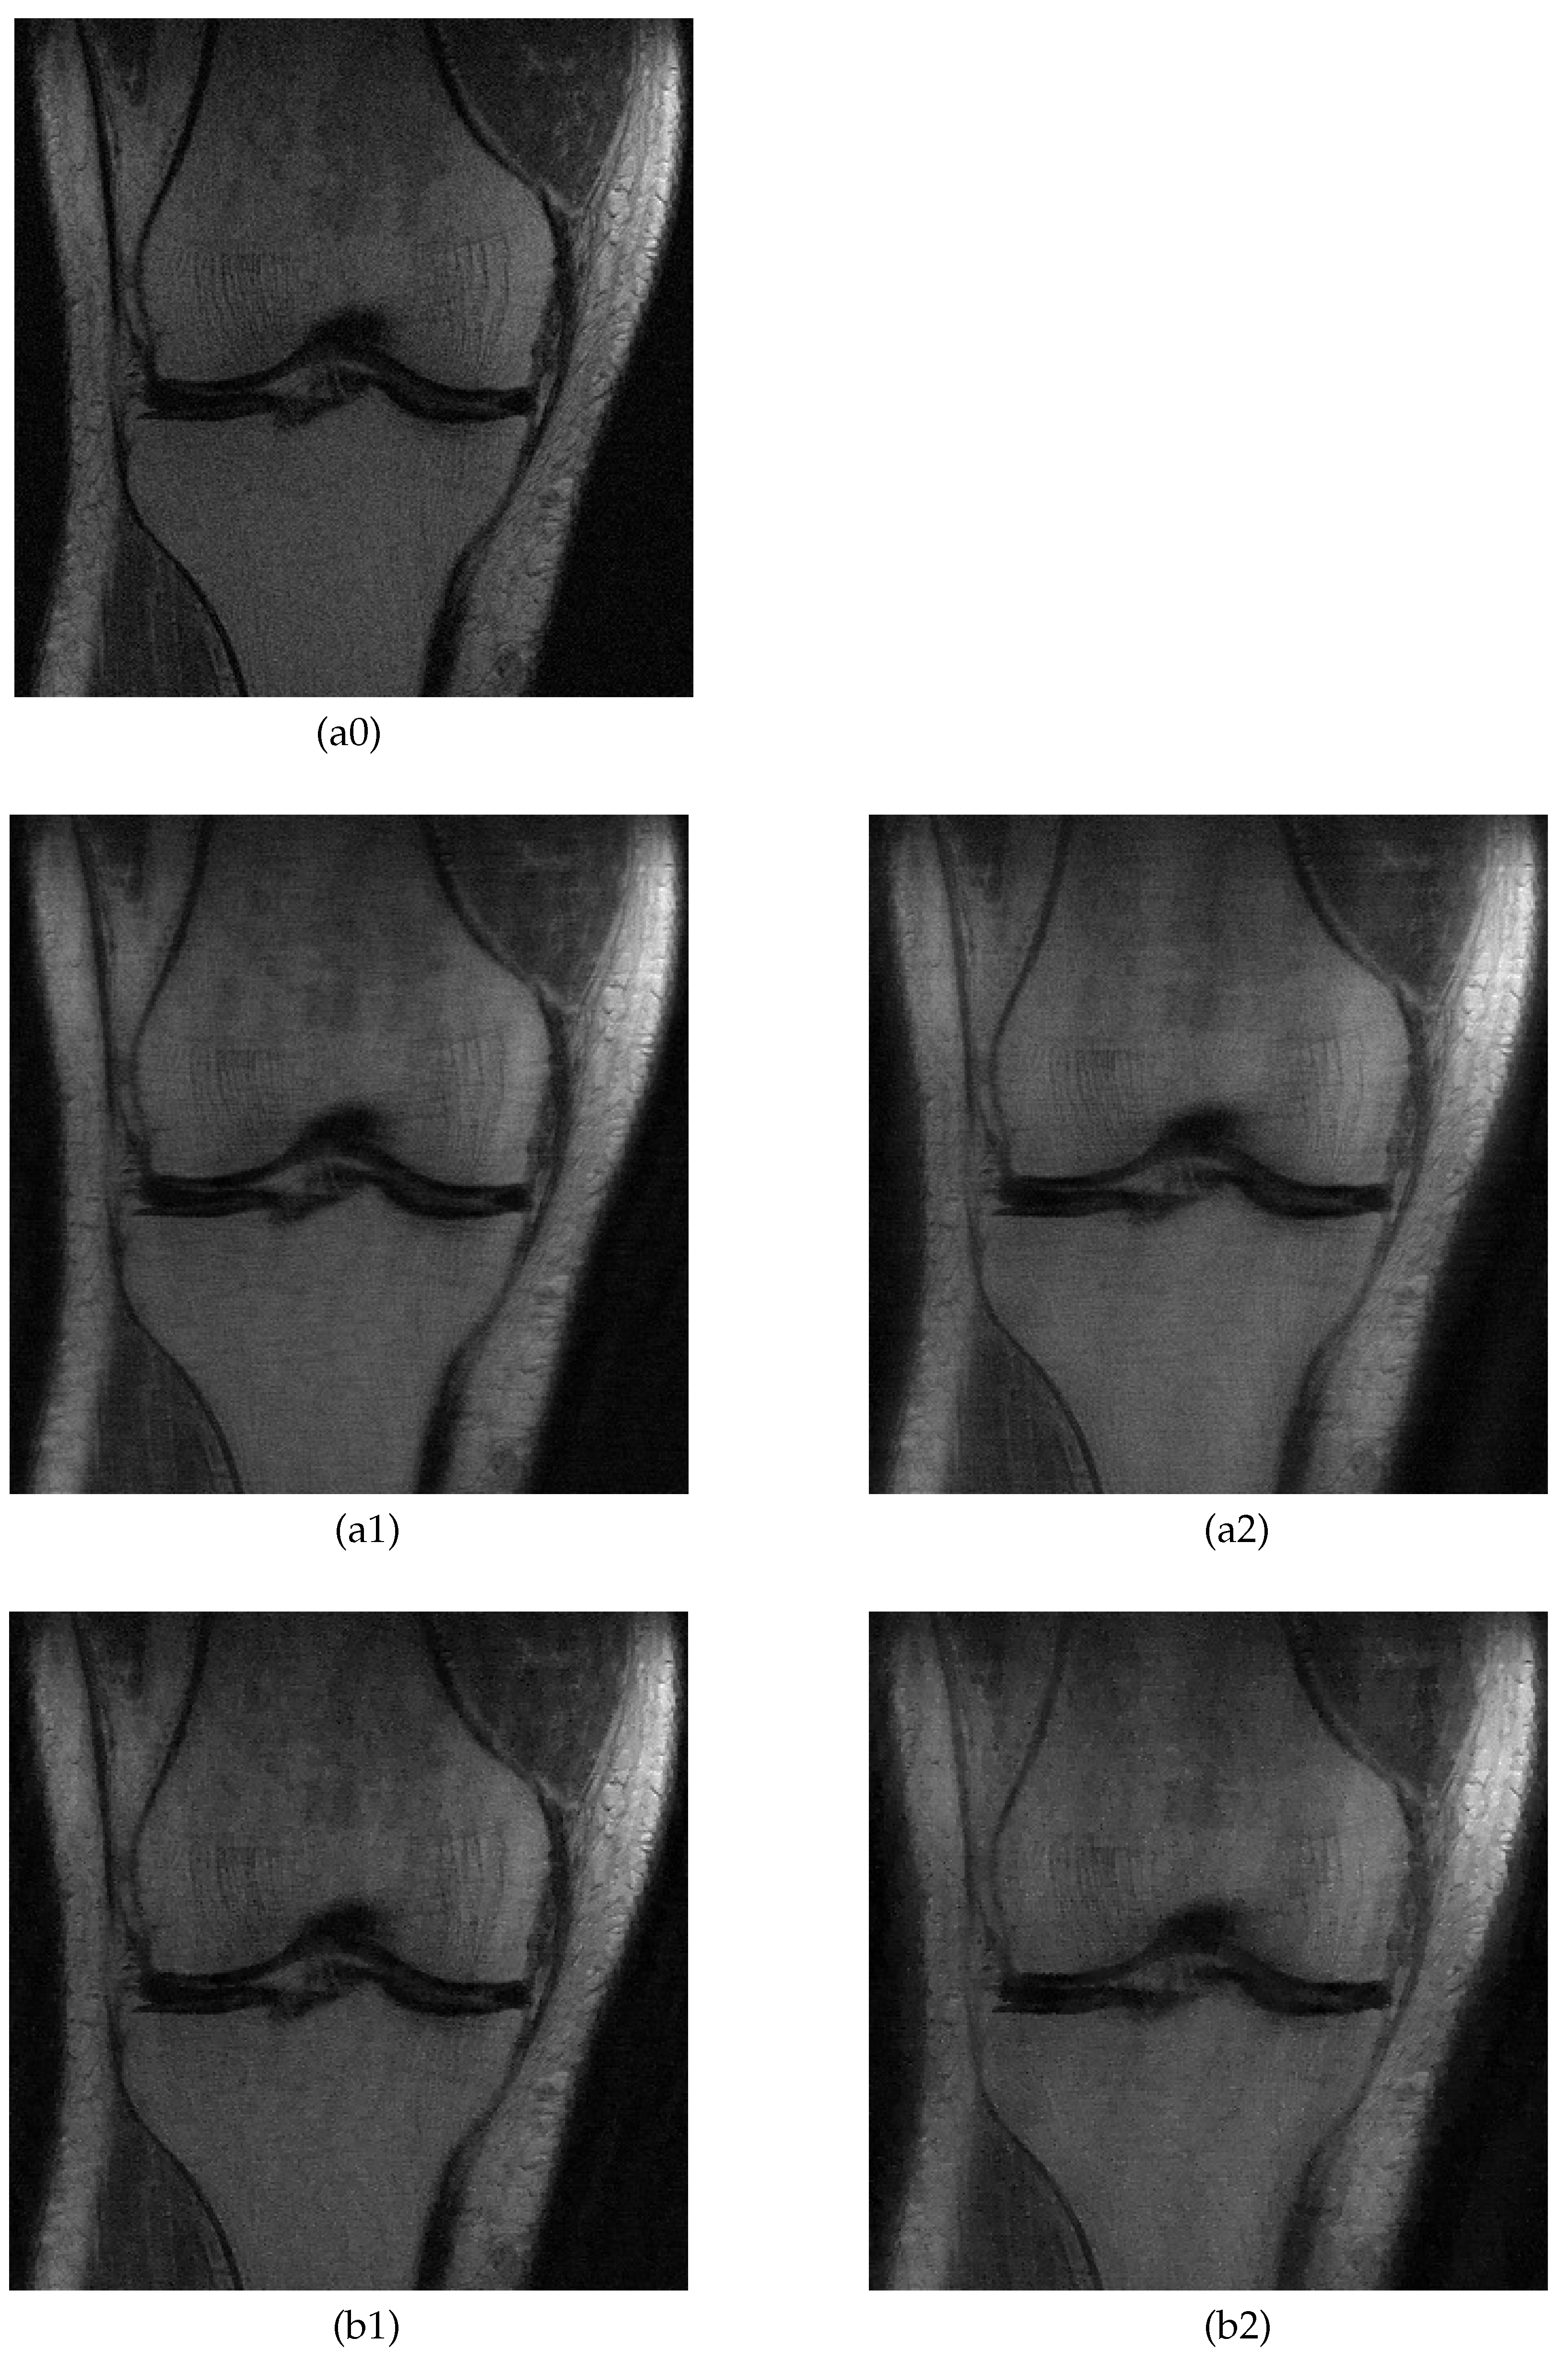

5.2. MRI Image Recovery

| Knee A | 28.5 | 26.4 | 0.657 | 0.570 | 28.2 | 24.5 | 0.615 | 0.538 |

| Knee B | 28.4 | 26.1 | 0.635 | 0.535 | 27.8 | 24.1 | 0.625 | 0.541 |